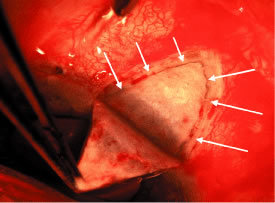

To obtain increasingly lower IOP, it is necessary to modify surgical technique (Table 15). By performing guarded filtration procedures so that the sutures can be released postoperatively, with the use of either laserable or releasable sutures, a lower final IOP can be obtained in some cases. This technique allows a bleb to develop that is similar to that seen in a full-thickness filtration procedure. Such blebs tend to be thin, polycystic, and located directly at the limbus, in contrast to those seen after classic trabeculectomy, which are thicker, lower, more diffuse, and more posterior. When antifibrosis agents (antimetabolites and corticosteroids) are added to procedures designed to develop full-thickness filtration, IOP tends to be sharply reduced.27–29 The blebs associated with the use of 5-fluorouracil (5-FU) and mitomycin are an exaggeration of the full-thickness type of bleb: Often, they are extensive, sometimes involving 360 degrees of the anterior surface of the globe, and the conjunctiva tends to be thin and completely ischemic.30–34

The thin filtration blebs associated with the use of mitomycin or 5-FU may rupture spontaneously. They tend to be so high that the adjacent cornea becomes dry, with the development of an uncomfortable delle. Ptosis tends to develop, and patients often are photophobia One of the most serious concerns is the high incidence of endophthalmitis in patients with thin blebs. When full-thickness blebs were the routine type of glaucoma procedure, endophthalmitis would develop in approximately 1% of patients. When 5-FU was used to develop filtration blebs inferiorly, an 8% rate of endophthalmitis was reported.35–42 Hypotony, even in the absence of a thin bleb, introduces serious problems. The soft eye does not maintain a constant optical state, and it has a constantly changing amount of astigmatism that makes it impossible to correct. Each time the patient blinks, the amount of astigmatism changes. Macular and disc edema cause reduced central acuity and deterioration of the visual field, and the globe may have a constant, visceral ache. Patients with such eyes are not comfortable.